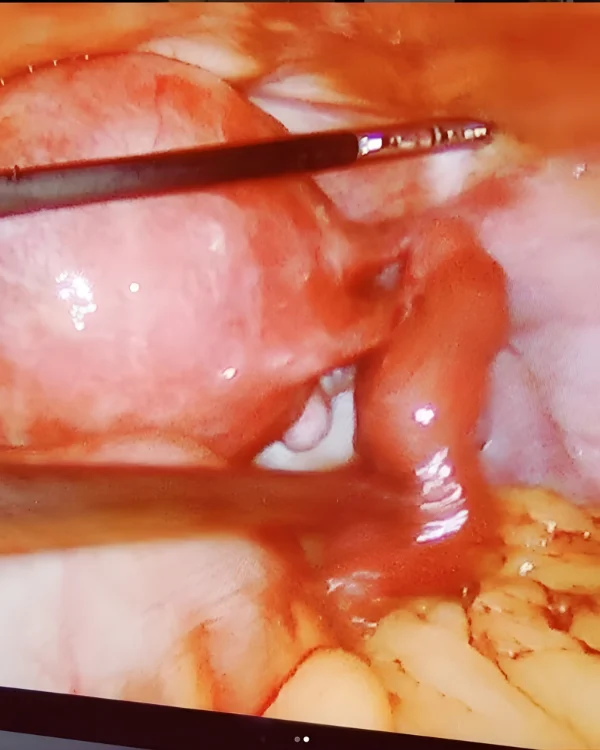

Advanced Laparoscopy

Robotic Surgery

Dr. Jasmin Rath specializes in modern, minimally invasive surgeries. She is an expert in Robotic Surgery, Laparoscopic Gynecological Surgery, and Hysteroscopy, often performing complex procedures like Myomectomy, Hysterectomy, and surgical Excision of Endometriosis.